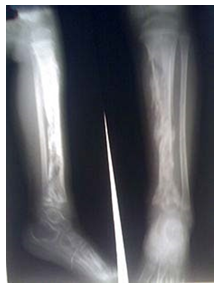

• Falaqa (falanga/bastinado)

•Soles of the feet are beaten with a blunt object whilst feet are tied to a pole  and raised

•Haemorrhage and oedema cause swelling of feet, may spread to lower

legs and knees.

•Thickening of plantar fascia, widening of heel fat pad, peripheral  neuropathy, scarring, pigmentation of soles of foot, instability of tarsal  bones, aseptic necrosis of metatarsals, malpositioning of the toes, rarely  fractures.